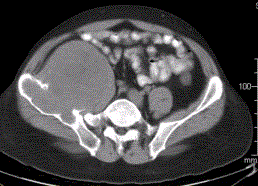

患者男,28岁,右下腹及臀部疼痛5个月余。查体:右髂骨外后侧压痛,右下腹可触及一软组织包块,质韧,固定。行骨盆正位CR、骨盆CT及MR扫描见下图。...

问题 患者男,28岁,右下腹及臀部疼痛5个月余。查体:右髂骨外后侧压痛,右下腹可触及一软组织包块,质韧,固定。行骨盆正位CR、骨盆CT及MR扫描见下图。 对于此病变的征象,描述不正确的是

选项 A.右髂骨翼分叶状溶骨性骨质破坏,边缘清晰硬化,形成巨大软组织肿块 B.右髂骨软组织肿块侵犯右侧腰大肌 C.右髂骨软组织肿块推压右侧腰大肌 D.T2WI示病灶内多发囊状高信号影 E.病灶内可见多发T1、T2均呈低信号的条状影,提示为纤维分隔

答案 B